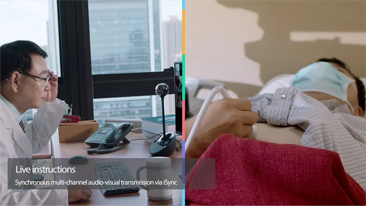

Since the company was founded, Mindray has been continuously exploring new ways to improve diagnostic confidence. Powered by the most revolutionary ZONE Sonography? Technology, Resona 7ŌĆÖs new ZST+ platform brings ultrasound image quality to a higher level by zone acquisition and channel data processing.

As well as the premium level image quality, Resona 7 also enhances clinical research capabilities with the revolutionary V Flow for vascular hemodynamic evaluation, and the most intelligent plane acquisition from 3D datasets for fetal CNS diagnosis. Combining the most intuitive gesture-based multi-touch operation and all the essential clinical features, Resona 7 is truly leading new waves in ultrasound innovation.